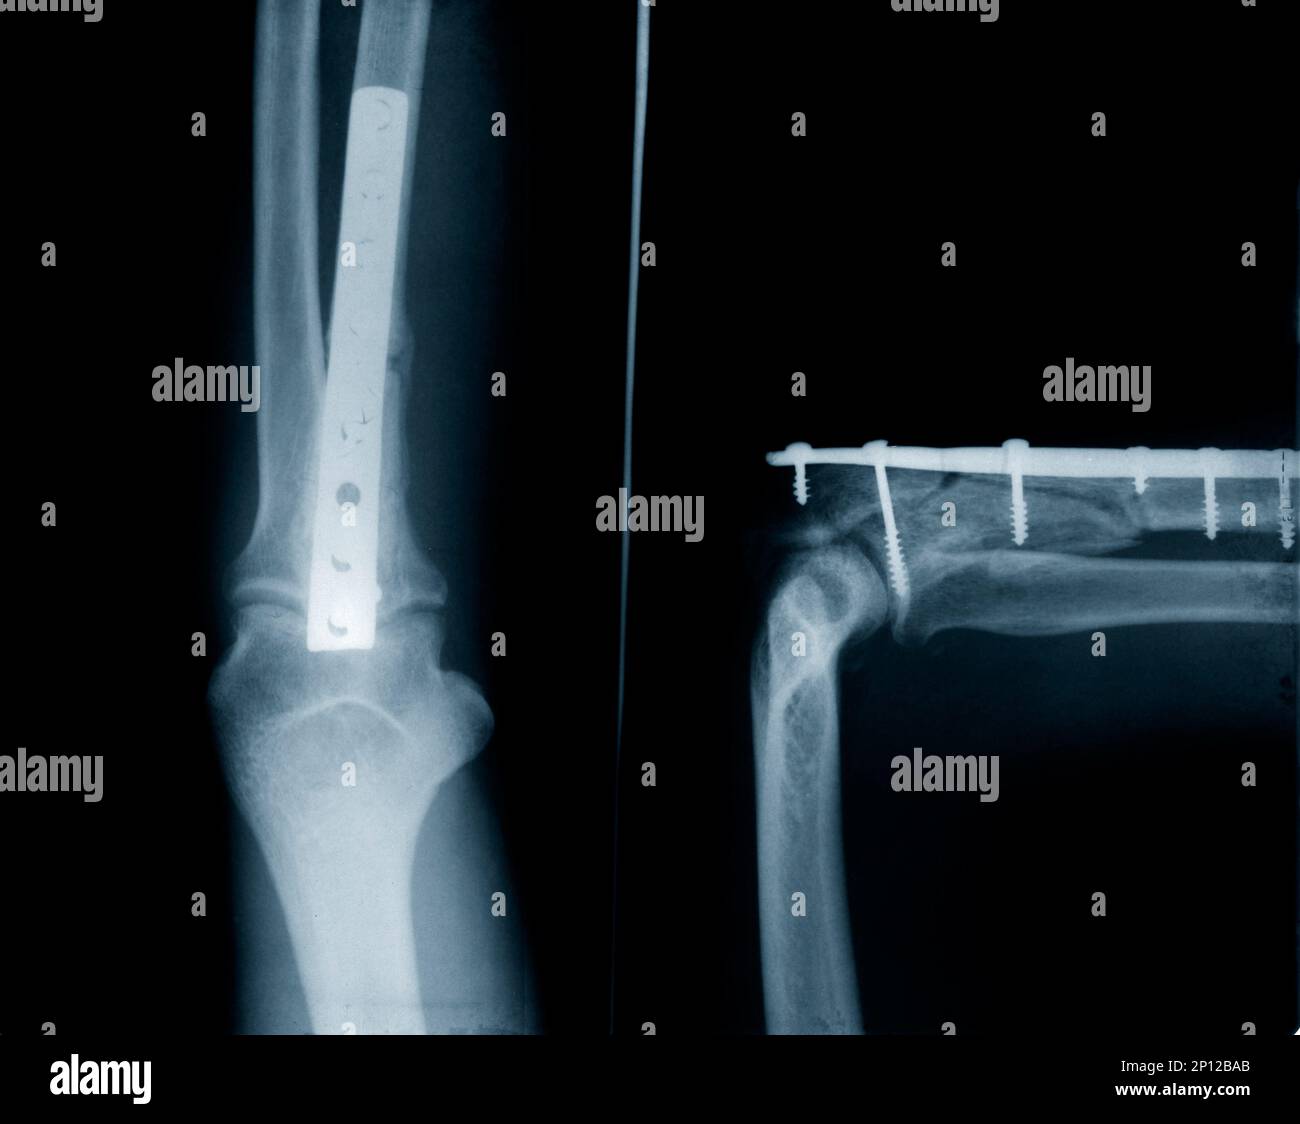

From www.alamy.com

Xray of ulna fracture implants with screws Stock Photo Alamy Hairline Fracture Ulna X Ray Most fractures of the radius or ulna seen by family physicians are distal radius, midshaft, or radial head fractures. A forearm fracture can occur in one or both of the forearm bones. Surgery may be necessary in some cases. The forearm is made up of two bones, the ulna and the radius. Radius and ulnar shaft fractures, also known as. Hairline Fracture Ulna X Ray.